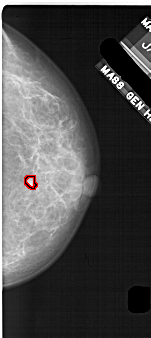

A_1708_1.RIGHT_CC

RIGHT_CC LINES 5056 PIXELS_PER_LINE 2251 BITS_PER_PIXEL 12 RESOLUTION 43.5 OVERLAY

FILE: A_1708_1.RIGHT_CC.OVERLAY

TOTAL_ABNORMALITIES 1

ABNORMALITY 1

LESION_TYPE MASS SHAPE IRREGULAR MARGINS ILL_DEFINED

ASSESSMENT 4

SUBTLETY 1

PATHOLOGY BENIGN

TOTAL_OUTLINES 1

BOUNDARY